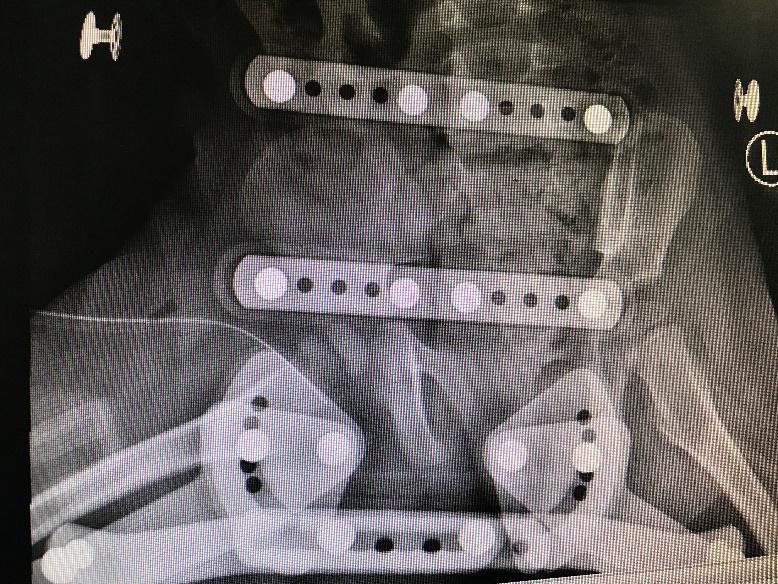

1 资料与方法 1.1 一般资料本研究为回顾性研究,获得医院医学伦理委员会审批(审编号:2020-IRB-035),通过检索本院的电子病例系统,搜索2016年1月1日至2018年12月31日期间出院诊断为“化脓性髋关节炎”的所有病例信息。纳入标准:(1)患儿临床症状、体征、影像学检查、关节液液培养、关节腔液白细胞计数(计数≥50 000 / mm3)、手术或病理证实的化脓性髋关节炎,见图 1~4;(2)关节腔穿刺或手术可见脓性标本。排除标准:(1)年龄>3岁;(2)穿刺或手术未能取得足够标本送检细菌培养者。

| 图 1 B超示关节腔内积液 |